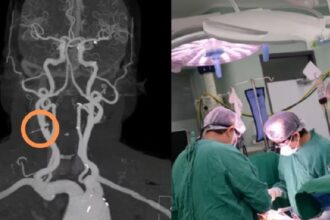

Fue al hospital tras comerse una bolsa de chicharrones y descubrieron que tenía un clavo en la carótida

Una mujer se llevó algo más que un simple susto luego que…